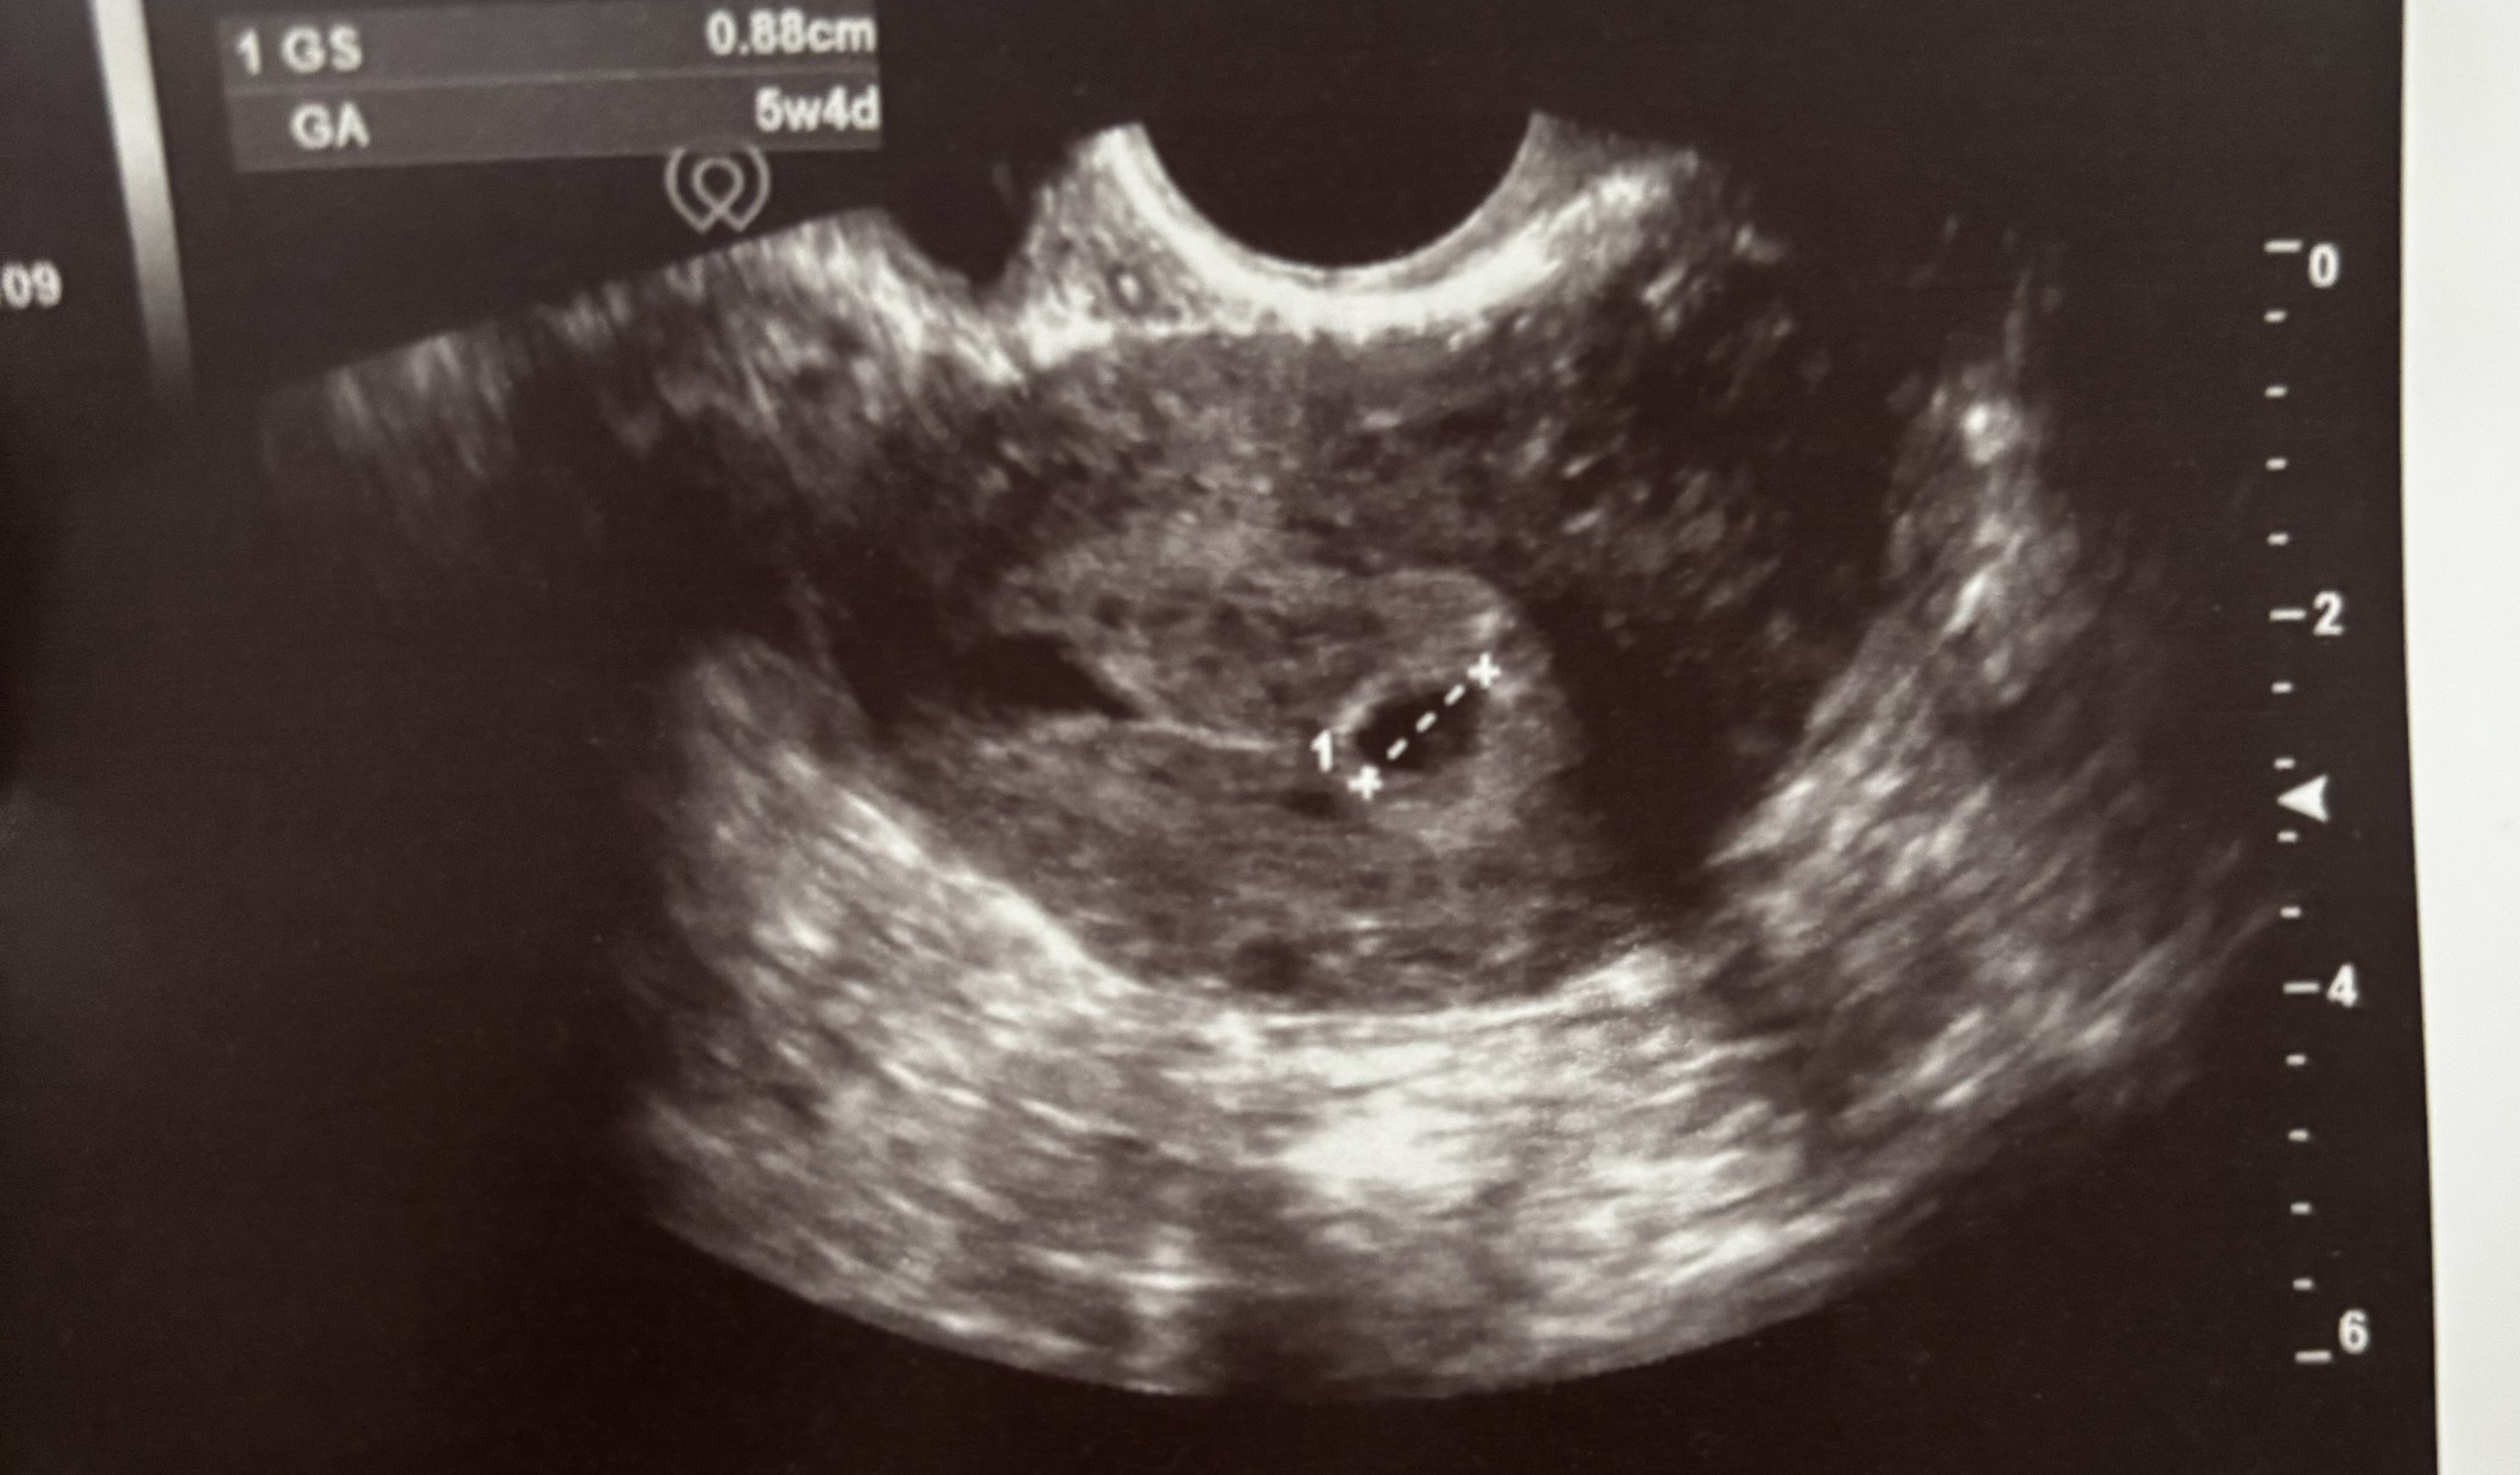

Ostatnia miesiączka zaczęła się 01.05. Byłam u ginekologa na wizycie kontrolnej po poronieniu 15.05 i twierdził, że owulacja będzie mieć miejsce za ok 3 dni.

Poniedziałek 3.06 122 / środa 5.06 293 / poniedziałek 10.06 1631 .

Na zdjęciu niestety za dużo nie widać, lekarz mówił, że trzeba czasu czy waszym zdaniem jest czym się martwić??